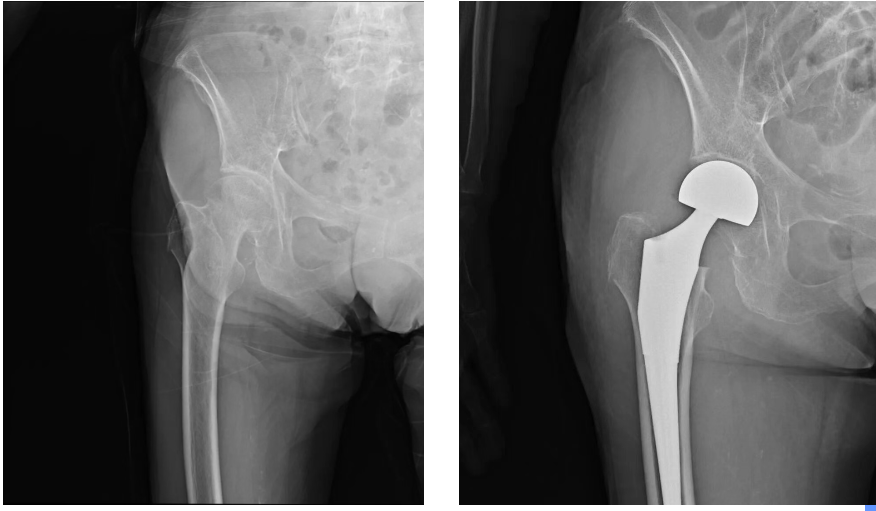

“做不做手术?”这个问题,牵动着所有人的心。保守治疗意味着长期卧床,对高龄患者而言,深静脉血栓、压疮、肺部感染加重等并发症风险极高。完善各项检查后,骨外科Ⅱ副主任医师黄大社与家属充分沟通、反复研判,最终家属同意为李奶奶采取手术治疗。

医院立刻启动多学科协作(MDT)机制。骨科、麻醉科、心血管内科、呼吸与危重症医学科、神经内科等科室骨干迅速集结,围绕“保障安全、精准治疗、快速康复”的核心目标,进行了多轮深入评估与讨论,最终制定“右股骨头置换术+右前臂高分子夹板固定”方案,并配套周密的围手术期快速康复(ERAS)计划。在手术团队的精湛操作和严密配合下,手术顺利完成。